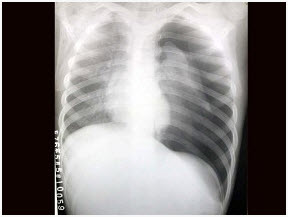

患者,男,3岁,突发左侧胸痛伴呼吸困难3小时入院,如图所示,最可能的诊断为()

A . 左侧肺气肿

B . 左侧气胸

C . 左肺门淋巴结结核

D . 右肺小叶性肺炎

E . 以上都不正确